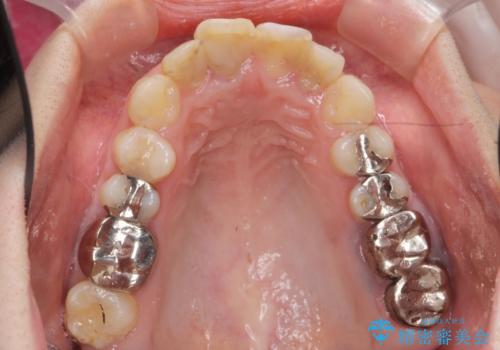

インプラント・セラミック・矯正治療を含む包括歯科診療

- 20代女性

- 治療計画

- 「地元の歯医者にずっと通っているが、どんどん歯が悪くなる。時間とお金がかかってもいいので徹底的に歯を治したい。」

、と総合的な歯科治療を希望されて来院されました。

虫歯や咬合関係・歯槽骨の吸収・根尖病変・歯の欠損・複合的な問題を一つずつ解決し、

安定した噛み合わせの構築・歯ブラシのしやすい環境の整備・歯内歯周の感染除去・造骨を伴うインプラント治療

を行い、長期的な予後を見込める口腔内環境を確立、整備して行きます。